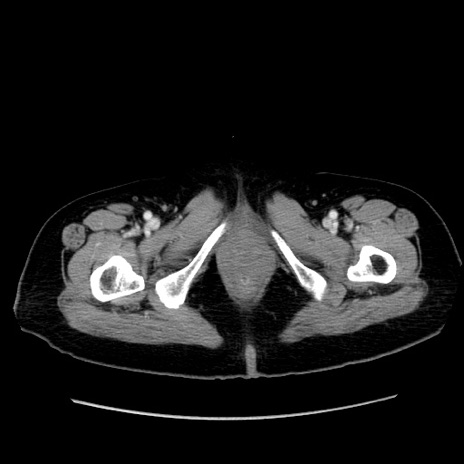

症例19(横断像)

【症例】80歳代女性

【主訴】下腹部痛

【現病歴】約8時間前より下腹部痛の出現あり、救急外来受診。

【既往歴】両側付属器切除

【身体所見】意識清明、下腹部正中に手術痕あり、その部位に一致して圧痛と反跳痛あり。腸蠕動音は亢進。

【データ】WBC 9300、CRP 0.15